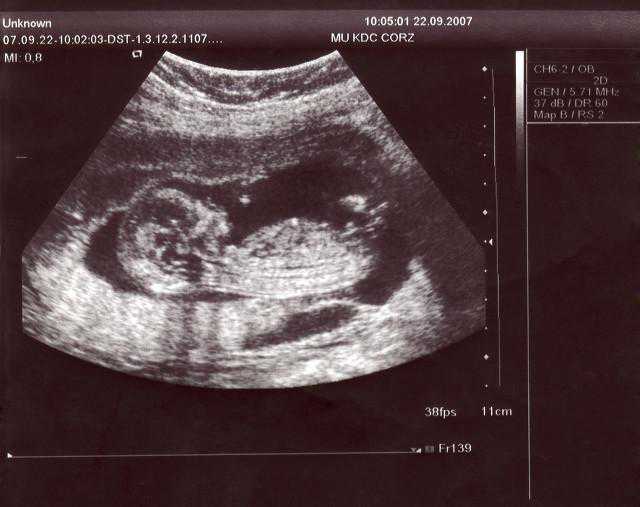

11周一13周6天NT超声检查

这时候我们做超声检查主要是观察宝宝是否存活,有没有大的,明显的或者说较为严重的结构畸形,胎儿的附属物,如胎盘的位置,成熟度,羊水量的大体评估等等,最重要的就是测量胎儿颈项透明层厚度也就是我们常说的NT厚度,因为NT的增厚与染色体异常所致的疾病高度关联,当然,只是高度“关联”哈,并不是说NT增厚就一定有问题,只是说大概率有问题,那么接下来就要择机进一步检查,比如无创DNA或羊水穿刺查染色体等,最后还要测量宝宝的头臀径估测当前孕周,进行末次月经的矫正及预产期的推算。